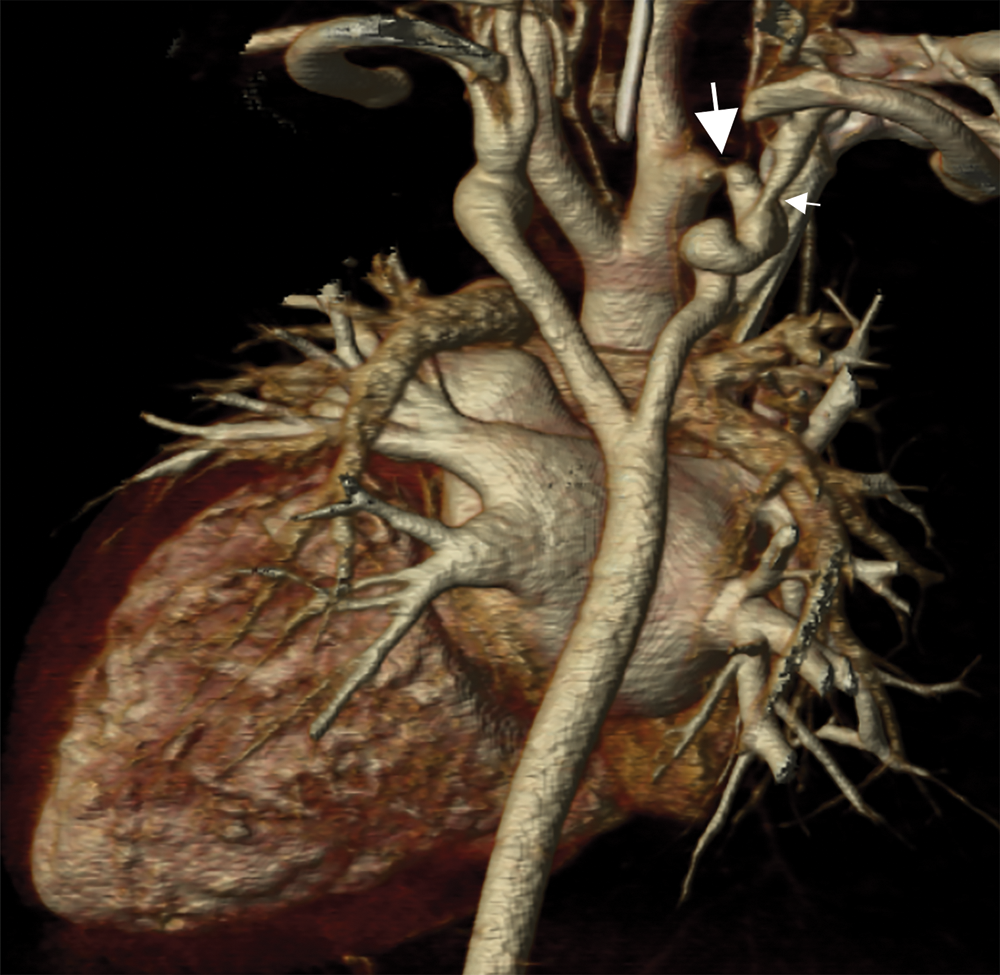

Cardiac CT (Figs. 2–4) identified an ascending aorta that gave rise to dilated common carotid arteries and an extremely tortuous and stenotic right aortic arch. The right subclavian artery originated beyond the area of severe arch stenosis with an additional area of narrowing at its origin. Collateral vessels were seen in the right side of the neck. A long and relatively narrow right-sided dorsal aortic root passed in a caudal direction where it was joined by an equally long but larger left-sided dorsal aortic root reflecting ductal flow in utero. The dorsal roots fused below the level of the carina. The descending aorta was also right-sided but crossed to the left at the level of the diaphragm. The left-sided dorsal root remnant supplied an aberrant left subclavian artery, a dilated left vertebral artery, and collateral vessels in the left side of the neck. There was no evidence of a double aortic arch.

Both the right subclavian artery and aberrant left subclavian artery were distal to the coarctation, making the measurement of extremity blood pressures unhelpful and falsely reassuring in determination of an arch gradient. Only the carotid arteries were directly supplied from the ascending aorta. Simultaneous invasive measurements of pressures in the carotid and femoral arteries in the OR revealed a 60 mmHg arch gradient.

Figure 3: A coronal 3D reconstruction viewed from posterior, shows stenosis of the right sided arch (large arrow), and stenosis of the proximal right subclavian artery (small arrow). The dorsal aortic roots are long and the left sided dorsal root is larger than the right indicating ductal flow in utero